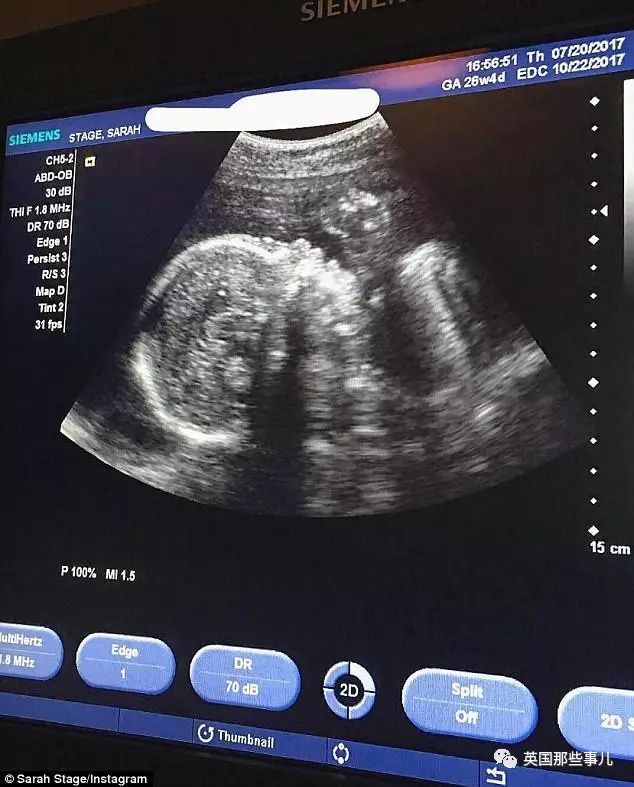

2天前,她去医院做常规的孕检…

发现宝宝已经两磅多重,而且心跳强劲有力,目前很健康…